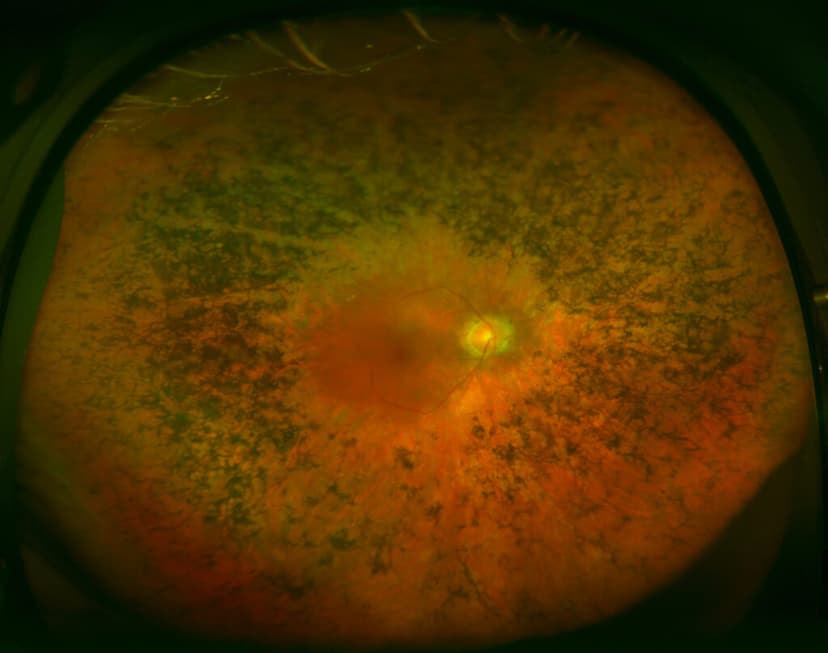

Viêm võng mạc sắc tố là tình trạng quáng gà, là tập hợp các bệnh có ảnh hưởng tới võng mạc của người bệnh. Khi soi đáy mắt, phát hiện biểu mô sắc tố dạng tế bào xương nằm ở xích đạo võng mạc, động mạch co nhỏ, gai thị nhợt màu có dạng sáp, đụng thủy tinh thể ở dưới bao sau, vẩn đục dịch kính… Bệnh thường phá hủy tế bào trong võng mạc, khiến cho thị lực suy giảm dần và dẫn tới mù lòa.